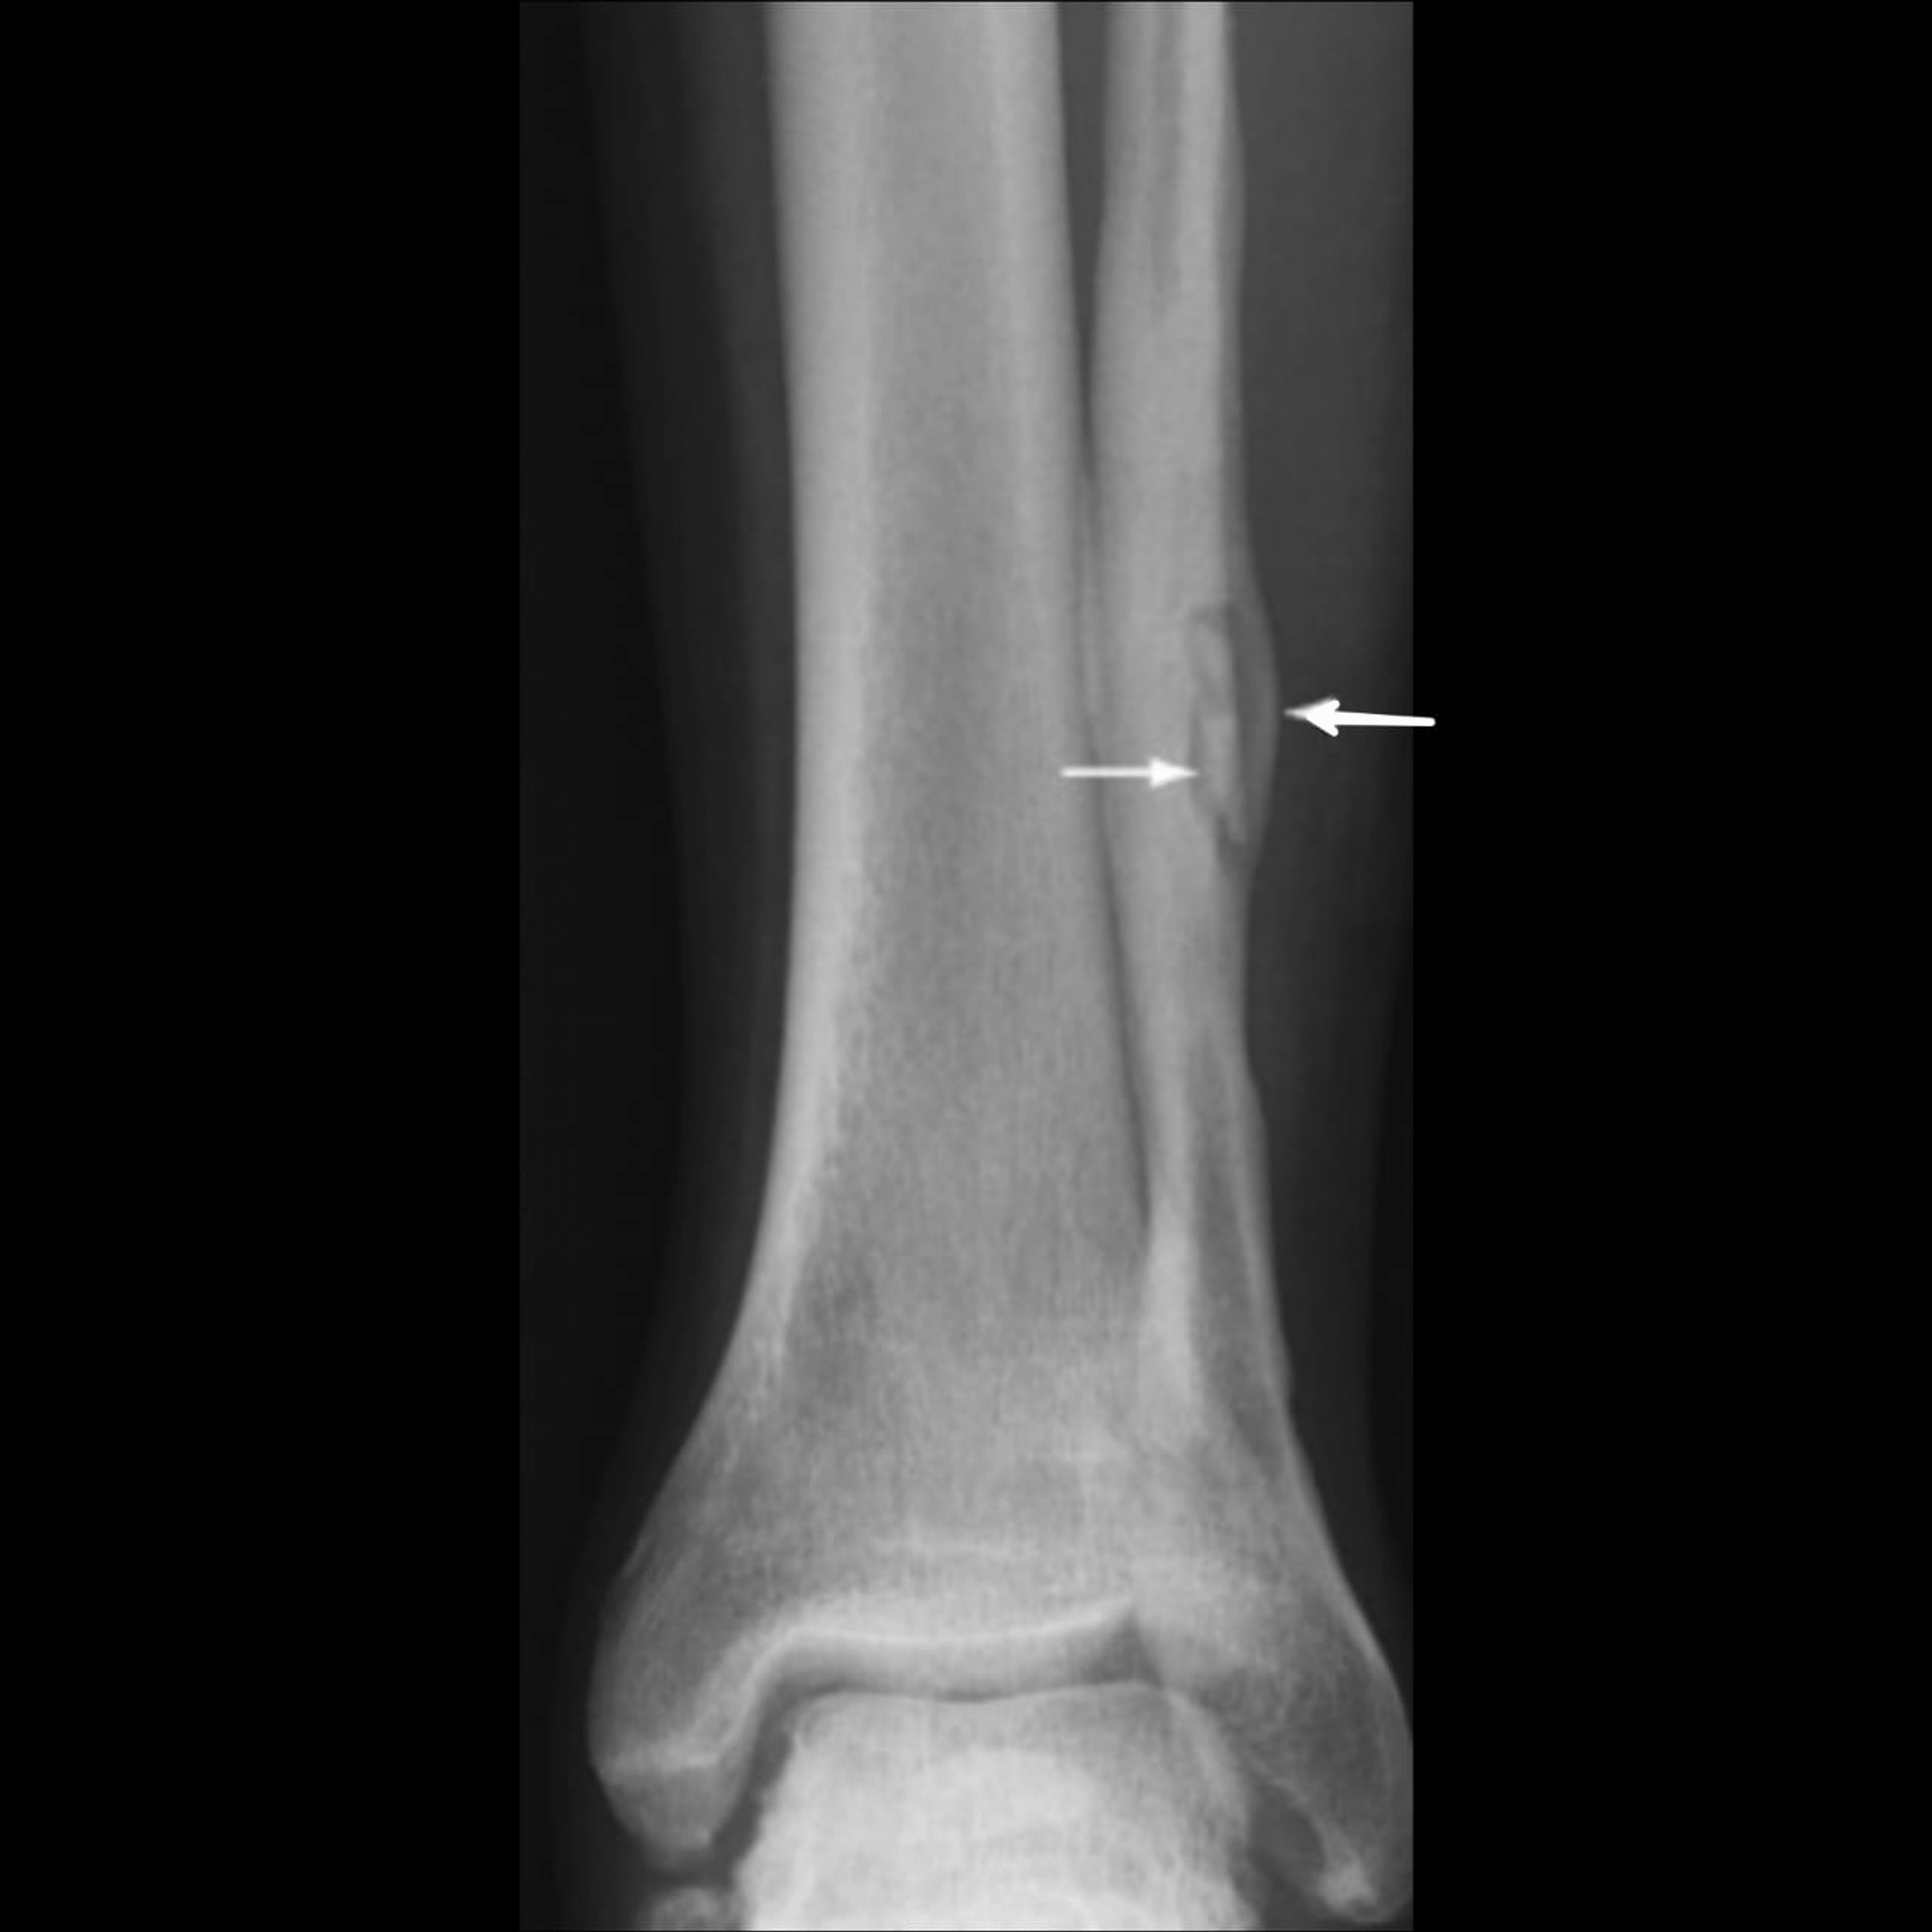

What Is Osteomyelitis And How Does It Enter The Bone? Healthsoothe

Osteomyelitiswith Radiological features Dentistry and Medicine Osteomyelitis Gums Learn more about symptoms and diagnosis. osteomyelitis is a bone infection that happens when bacterial or fungal infections spread from other parts of your body into your bone marrow. two cases are reported of chronic osteomyelitis in healthy individuals with no adverse medical conditions. Odontogenic infections, consisting primarily of dental caries and periodontal disease (gingivitis and. osteomyelitis. Osteomyelitis Gums.